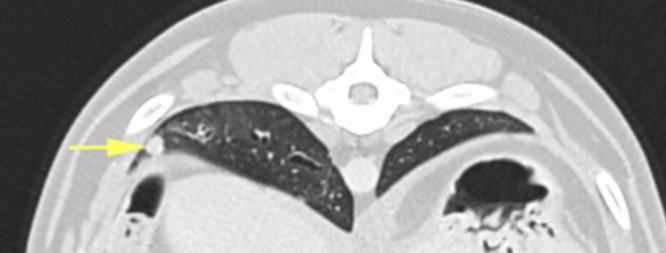

The pre-contrast images of the thorax showed a large bronchocentric mass in the right caudal lung lobe, with irregular contours (Image 5). There was one further smaller nodule in the periphery of the right caudal lung (Image 6). The cardiovascular, mediastinum and trachea all appeared normal.

Image 6: Small nodule in the right caudal lung lobe (arrow).